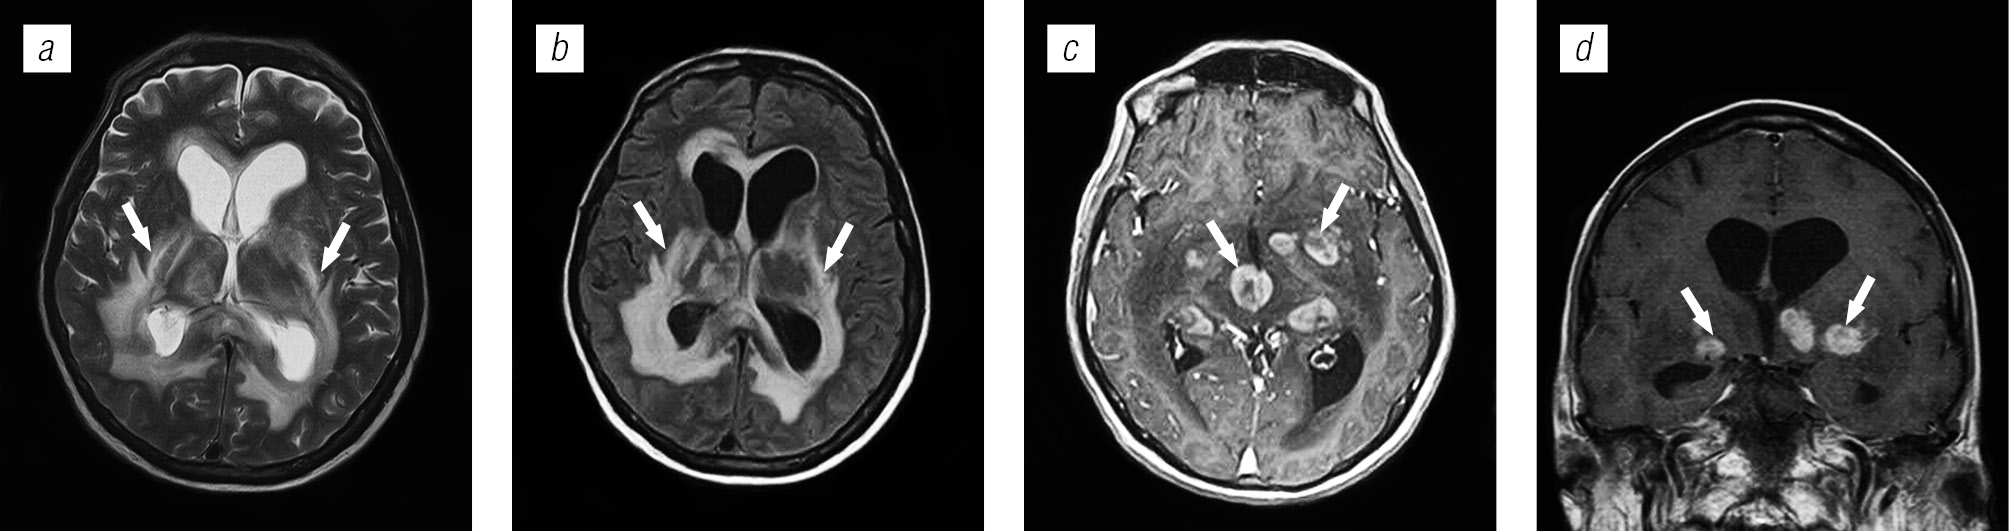

Структура оппортунистических и вторичных заболеваний была представлена токсоплазмозом головного мозга (18,3 %), герпесвирусными поражениями (12,2 %), прогрессирующей мультифокальной лейкоэнцефалопатией (10,24 %), нейроинфекцией неуточненной этиологии (12,2 %), криптококкозом (4,39 %), туберкулезом (2,44 %), лимфомой головного мозга (2,44 %), МАК-инфекцией (0,24 %).